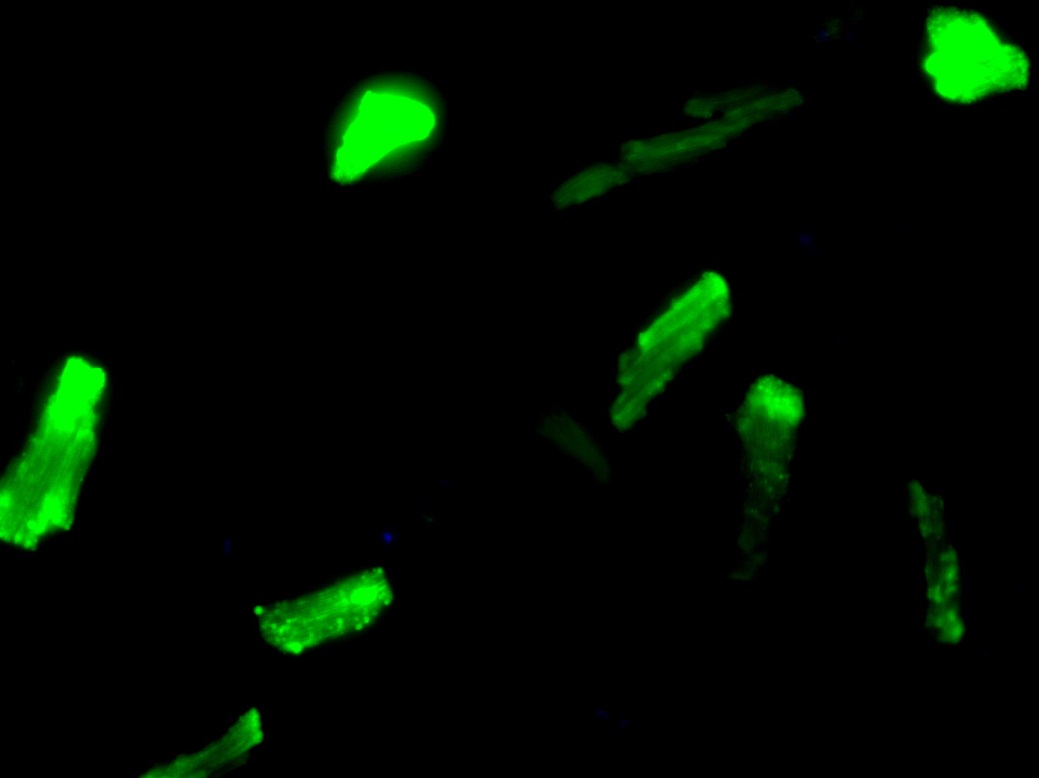

На рисунке: Активные формы кислорода в кардиомиоцитах после гипоксии/реоксигенации. Флуоресцентное окрашивание in vivo 2′,7′-дихлорфлуоресцеином, увеличение х400.

На рисунке: Влияние метаболического синдрома на образование активных форм кислорода в кардиомиоцитах крыс при гипоксии-реоксигенации. МС – диета-индуцированный метаболический синдром.

Также ученые обнаружили, что метаболический синдром способствует усилению окислительного стресса в кардиомиоцитах при гипоксии/реоксигенации. Полученные результаты позволяет выдвинуть гипотезу о том, что окислительный стресс может быть причиной низкой эффективности адаптационных процедур и агонистов мю-опиоидных рецепторов при метаболическом синдроме. Могут ли в данной ситуации антиоксиданты улучшить эффективность? Этот вопрос предстоит исследовать в дальнейшем.